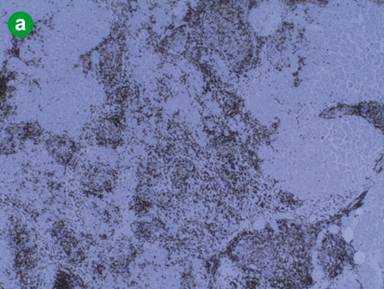

Macroscopic examination of the specimen showed an ill-defined whitish nodule measuring 1.5 cm in diameter in the uncinate and another in the body of the pancreas. The microscopic examination of this area in the body showed nodular lymphoid hyperplasia measuring 1.7x2.0 cm. The lymphoid tissue contained well-formed follicles and large germinal centers with macrophages surrounded by fibrotic stroma (Figure 1bc). The lymphoid follicles were mainly composed of large B cells in the center, with small T-cells at the periphery. A similar focus of nodular lymphoid hyperplasia was identified in the uncinate process measuring 1.5x1.8 cm in size. The tail of the pancreas was unremarkable apart from scattered small foci of lymphoid hyperplasia and a few areas low grade PanIN. Eighteen lymph nodes identified within the specimen were all normal. At this point the probable diagnosis of nodular lymphoid hyperplasia needed to be differentiated from follicular lymphoma (a mature B-cell lymphoma that is thought to originate from cells in the germinal center). Therefore, additional immunostains were performed (Figures 2 and 3). The follicular germinal centers showed CD10(+) and were negative for BCL2. CD21(+) and CD23(+) highlighted dendritic cell meshworks, whereas CD3(+) and CD5(+) showed small T-cells. Cyclin D1 appeared negative in lymphoid cells and kappa/lambda light chain restriction analysis did not reveal a monotypic lymphoid population. Therefore, the appearances confirmed the diagnosis of reactive inflammatory infiltrate and no malignancy. At follow-up, contrast enhanced CT of the chest, abdomen and pelvis 6 months post-operatively has shown no disease recurrence or new lesions.

Figure 2. Immunohistochemical staining revealed a follicular infiltrate which was composed of centers with cells expressing B-cell characteristics that were CD10 positive (a,) and BCL-2 negative (b.) (BCL-2 negativity implies reactive rather than neoplastic follicles), whilst CD21 (c.) and CD23 (d.) staining demonstrated regular and orderly network of follicular dendritic cells as in reactive lymphoid follicles, thus supporting the diagnosis of reactive lymphoid follicular hyperplasia. |